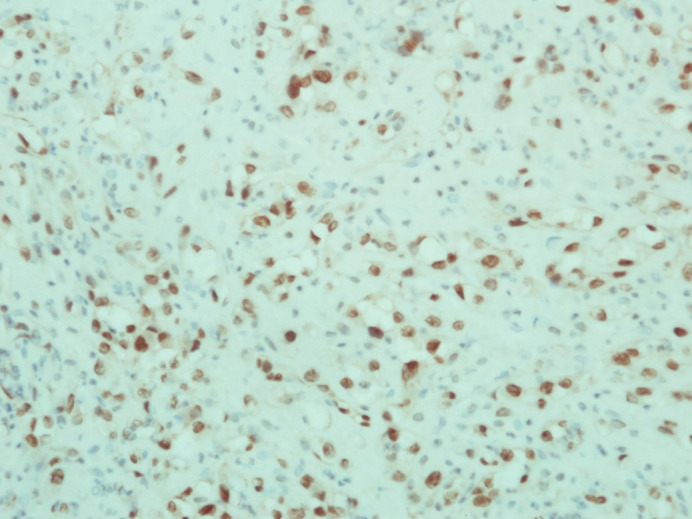

Thyroid angiosarcoma is an extraordinarily sparse malignancy, often populating alpine regions. Clinically, thyroid angiosarcomas tend to be nonspecific in presentation, starkly dependent on site, size, extension, and metastases. Tumors are locally aggressive and can present with sudden onset pain due to intra-nodular hemorrhage and compressive symptoms from sudden expansion. Due to the disease being a scarcely reported entity, there is little scholarship regarding its management. We report an interesting case of a 63-year-old man presenting with a swelling in the neck, incidentally found to be a thyroid angiosarcoma with a first-time reported associated spinal metastasis. The patient has a uniquely presenting thyroid angiosarcoma and is the first patient to present as such within a non-alpine South Asian region.